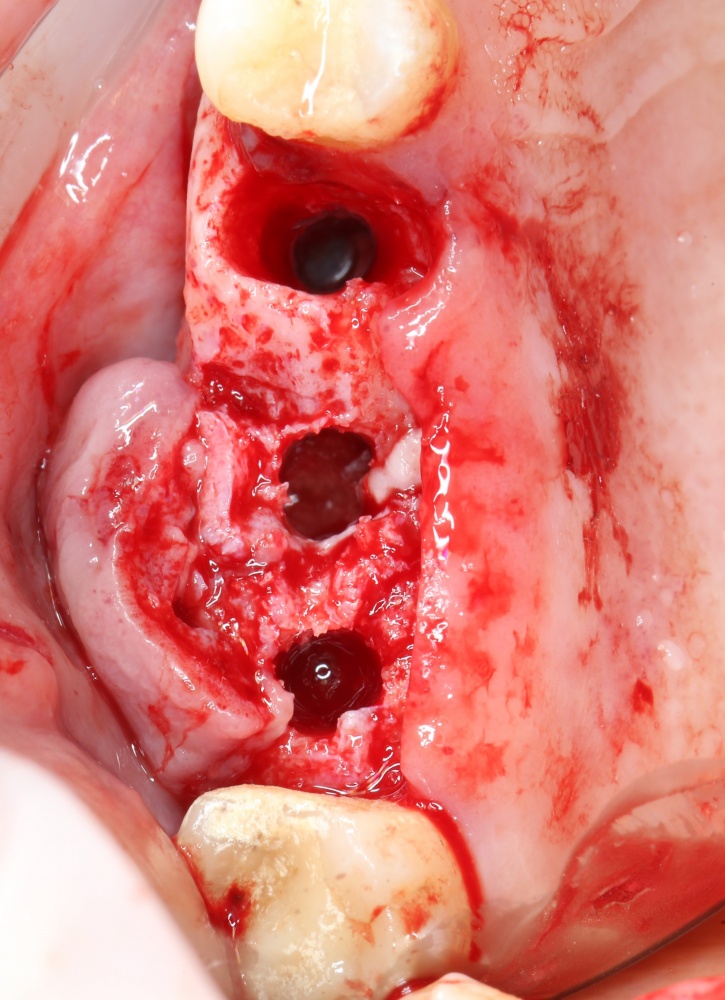

Кстати, обрати внимание на ширину альвеолярного гребня (левая картинка). Она чуть меньше 3 мм. Это объясняет, почему я засомневался в возможности установки имплантатов одновременно с остеопластикой. Понятно и без КЛКТ.

Возвращаемся к основной операционной области. Еще раз посмотрим на альвеолярный гребень, поофигеваем от его ширины и моих грандиозных планов:

Я зафиксировал костный блок практически без адаптации на несколько винтов. Обрати внимание, что винты находятся в зоне, где не планируется установка имплантатов. Фиксация должна быть надежной, поскольку мне еще предстояла подготовка лунок для имплантатов. Трех винтов для этого вполне достаточно.

Дальнейшая адаптация костного блока свелась к сглаживанию острых краев. После чего я приступил к подготовке лунок и установке имплантатов.

Установка имплантатов.

Напомню, что для этой работы я выбрал субкрестальные имплантаты Ankylos C/X. Они прекрасно сочетаются с любым методом остеопластики.

Я не планирую установку супраструктур или коронок, поэтому на уровень первичной стабильности можно положить болт. Даже наоборот — чем меньше крутящий момент при установке, тем лучше. Для имплантатов Ankylos и подобных им, это особенно важно. В общем, момент силы при установке — не более 10-15 Нсм.

Глянем на то, что получилось: